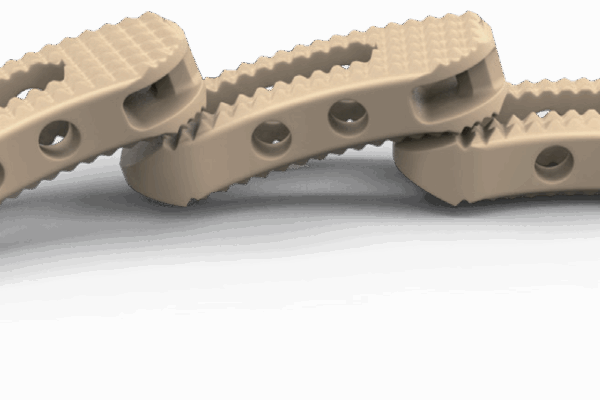

Sistema de cages para fusão intersomática, com diferentes modelos (Coales-P, C, M, T, L e Mesh), em PEEK, com marcadores de tântalo para melhor visualização e adesão óssea.

- Materiais: PEEK (ASTM F2026), Tântalo.

- Usos principais: Fusão espinhal lombar e cervical, oferecendo estabilidade e suporte biomecânico.

- Compatibilidade: Compatível com técnicas de fusão TLIF, PLIF, ACIF, etc.

Design anatômico • Radiotransparente • Marcadores de tântalo para visualização • Reduz risco de subsistência